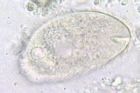

結腸小袋纖毛蟲生活史中有滋養體和包囊兩個時期。滋養體呈橢圓形,無色透明或淡灰略帶綠色,大小為30~200×25~120μm。全身披有纖毛,活的滋養體可借纖毛的擺動呈迅速旋轉式運動。蟲體極易變形,前端有一凹陷的胞口,下接漏斗狀胞咽,顆粒食物借胞口纖毛的運動進入蟲體,形成食物泡經消化後,殘渣經胞肛排出體外。屬纖毛蟲門、少膜綱、腹口亞綱、盾纖目。蟲體略成葵花籽形,長50-75чm,寬20-50чm,內質不透明,蟲體中、後部各有一伸縮泡(contractilevacuo1e)具有調節滲透壓的功能。蘇木素染色後可見一個腎形的大核和一個圓形的小核,後者位於前者的凹陷處。包囊圓形或橢圓形,直徑為40~60μm,淡黃或淡綠色,囊壁厚而透明,染色後可見胞核。